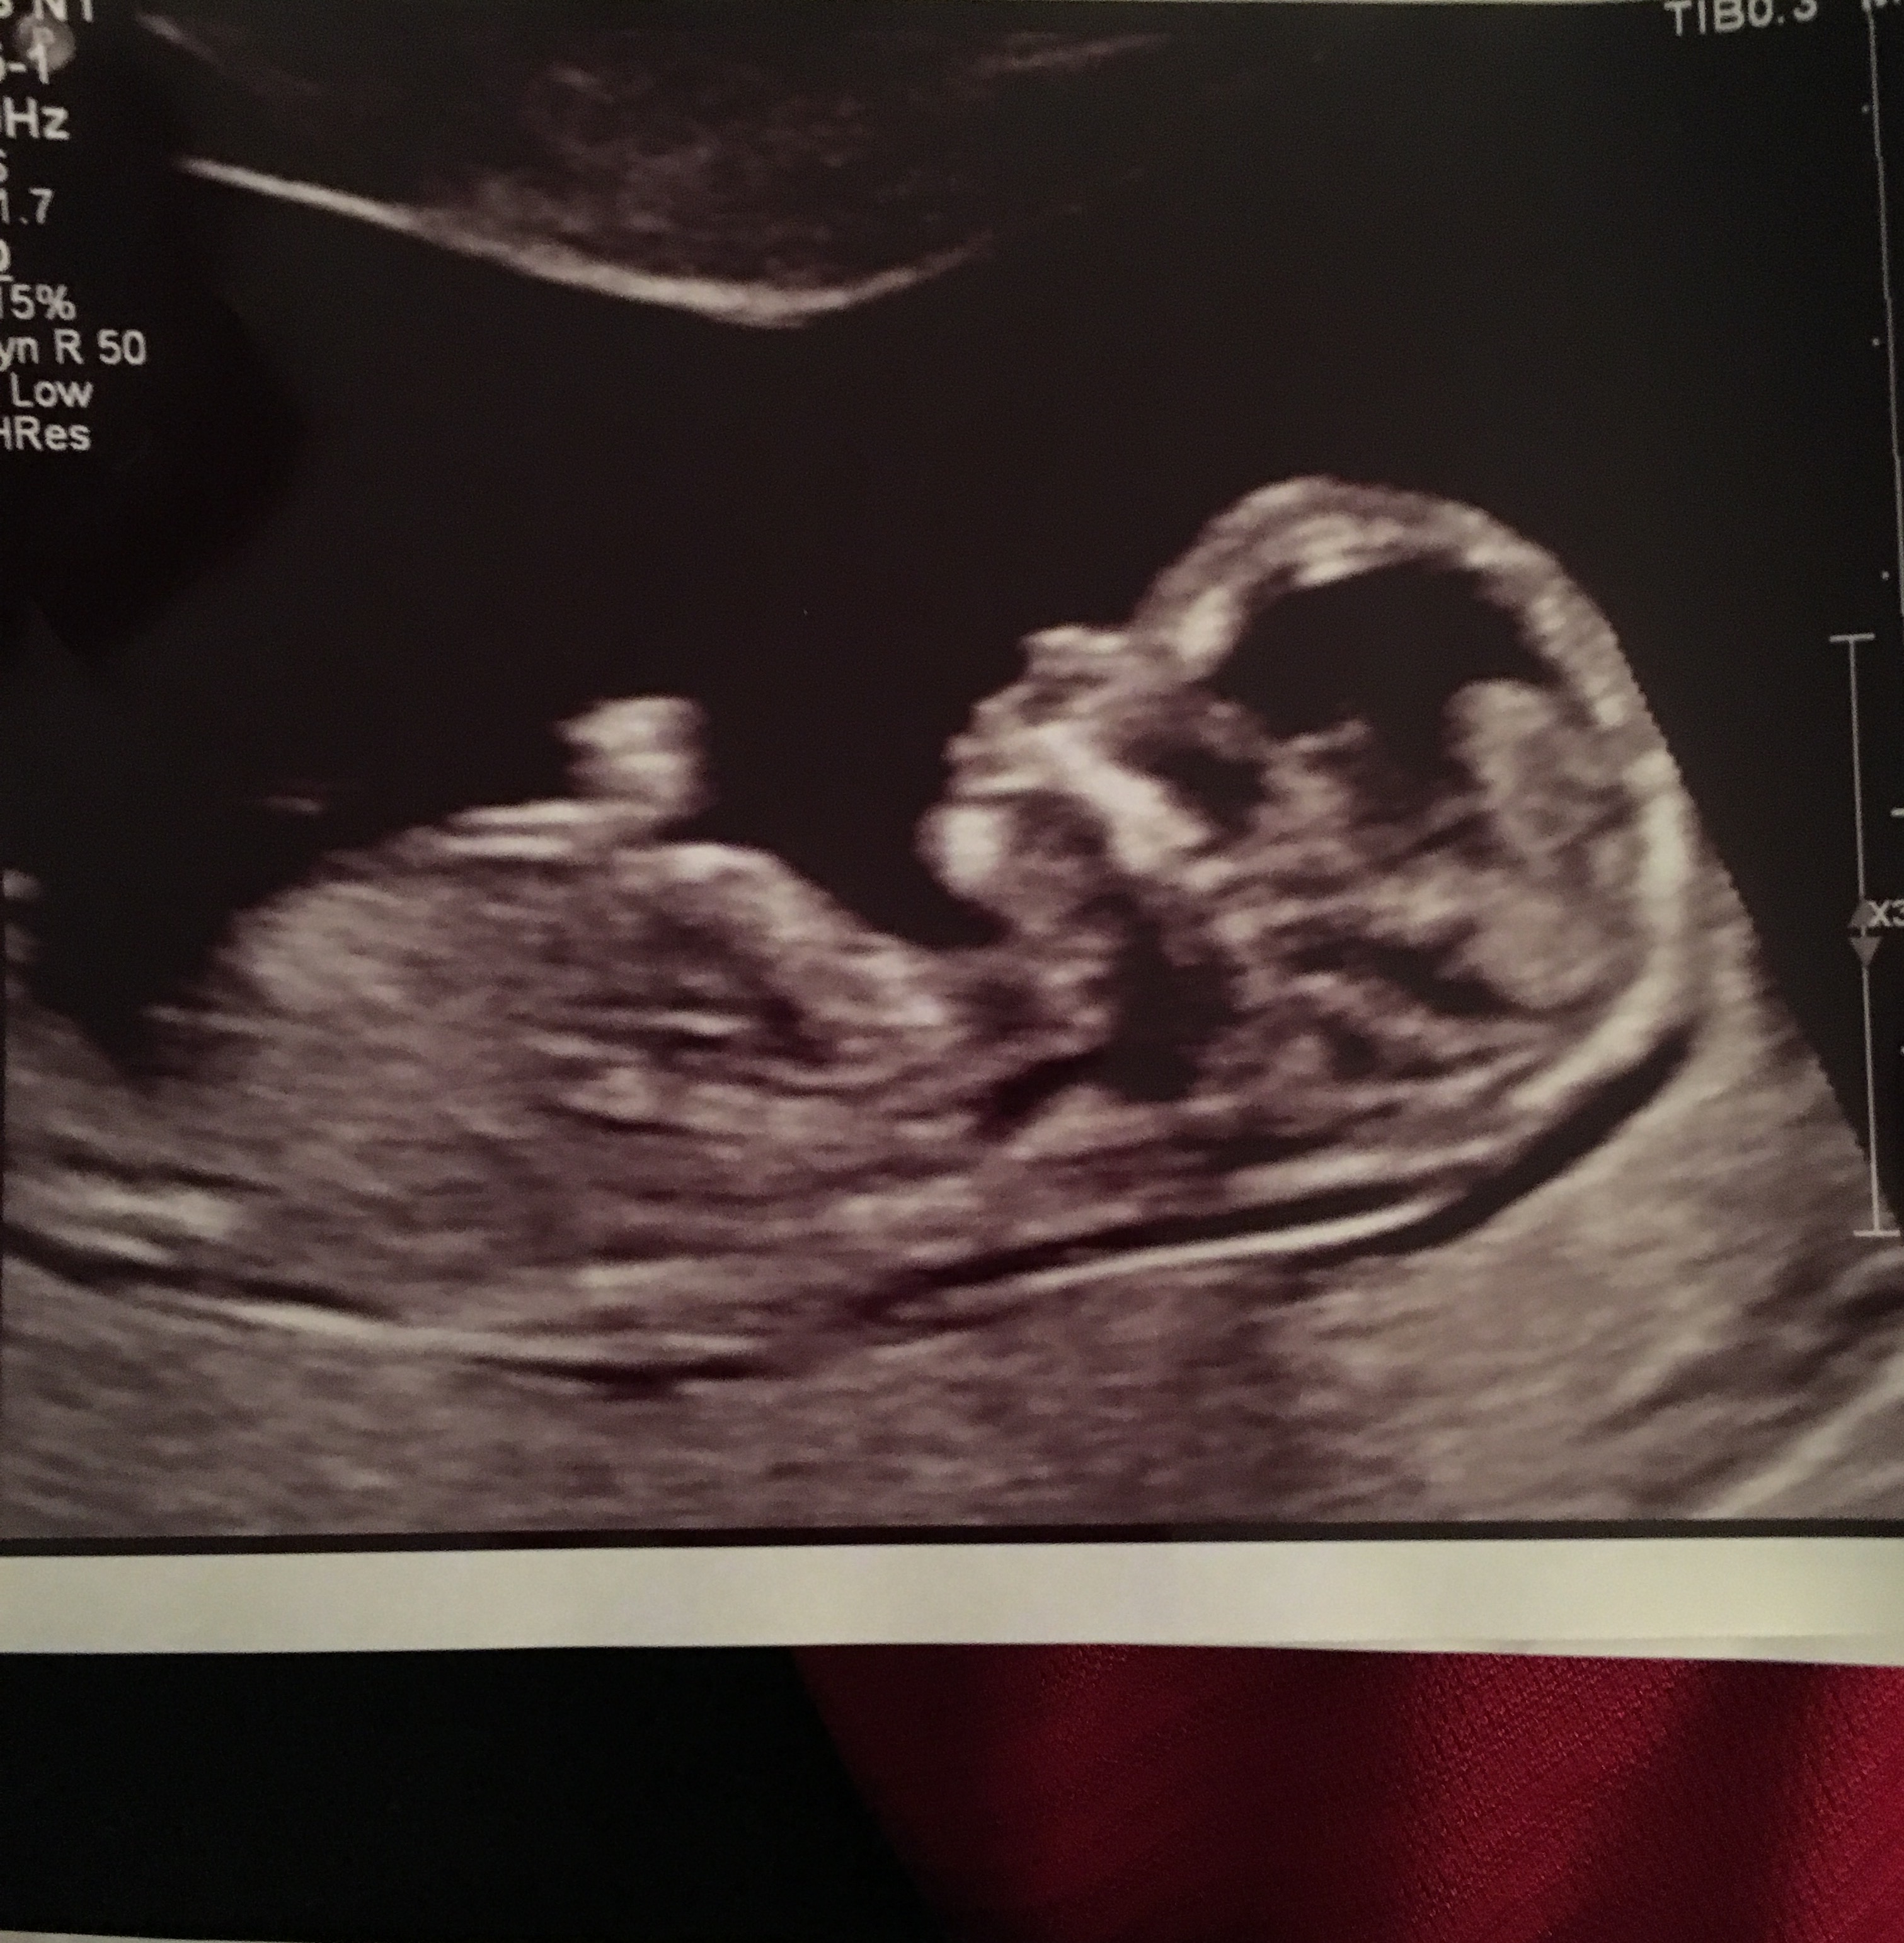

13 1/2 weeks! please help with guesses for boy or girl! Attachment 32340

Tentative girl

I can't see a nub sorry Sent from my SM-N920I using Tapatalk